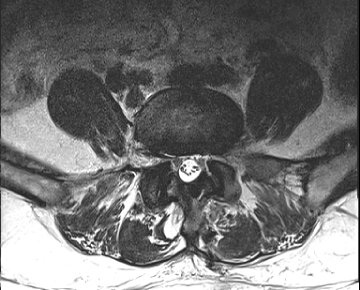

요추 협착증 수술 전·후

2020.08.30

2022.09.06

ㆍ환자 동의를 받은 자료이며, 이미지 사진은 실물과 다를 수 있습니다.

ㆍ모든 자료는 새움병원 자료입니다.